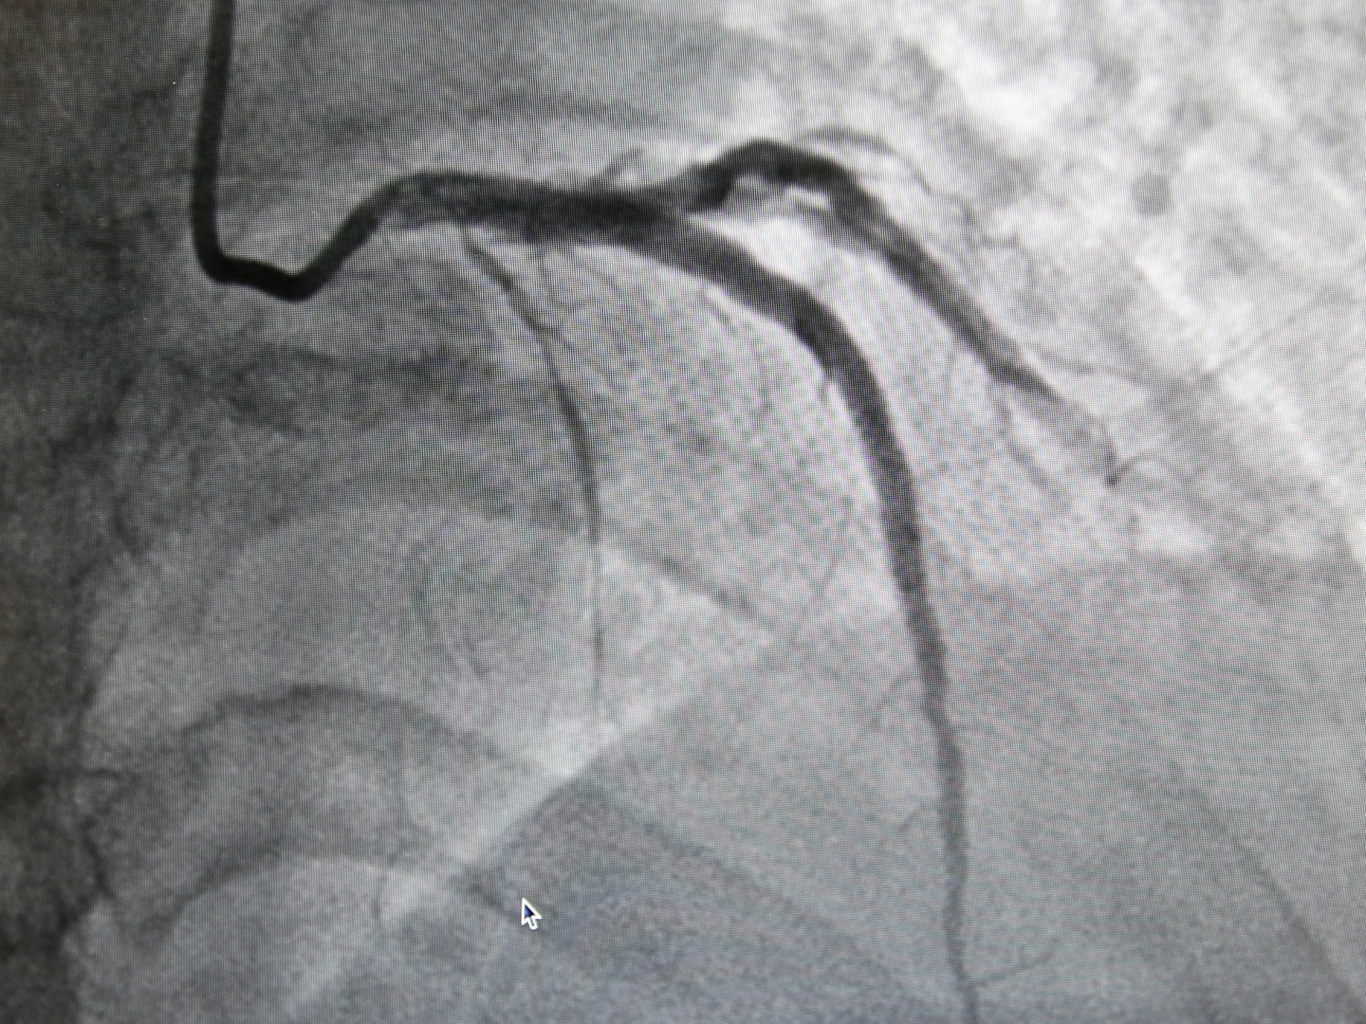

後來在一位同樣有背痛症狀的朋友建議下,張女士找到了花蓮慈院張懷仁醫師。張懷仁醫師表示,一開始很難診斷有心臟方面的問題,但是張女士提到說自己有胸悶的狀況,而且是對話一陣子就要停下來喘氣,讓張懷仁醫師擔心會不會真的是心血管的問題,結果安排心導管檢查後發現,張女士三條冠狀動脈血管中的左前降支,幾乎是完全阻塞,立即為張女士進行治療,並且放置兩條冠狀動脈血管支架。